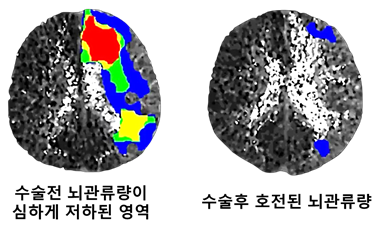

혈전제거술이 불가능하거나 실패한 급성 뇌경색 환자에게 응급 뇌혈관문합수술의 효과성과 안전성을 영상학적으로 뇌혈류의 정량적인 분석을 통해 입증된 연구도 있다.

분당서울대병원에서 발표한 논문에 따르면, 허혈성 모야모야병으로 수술받은 환자는 수술을 받지 않은 환자에 비해 현저히 낮은 뇌경색 발생 비율을 보이는 것으로 나타났다.